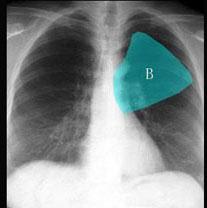

在图所示正常胸部X线影像图像上,该英文字母所代表的肺段为 ( )A、舌叶上段B、前段C、后段D、尖后段E、尖段

问题 在图所示正常胸部X线影像图像上,该英文字母所代表的肺段为 ( )

选项 A、舌叶上段 B、前段 C、后段 D、尖后段 E、尖段

答案 B